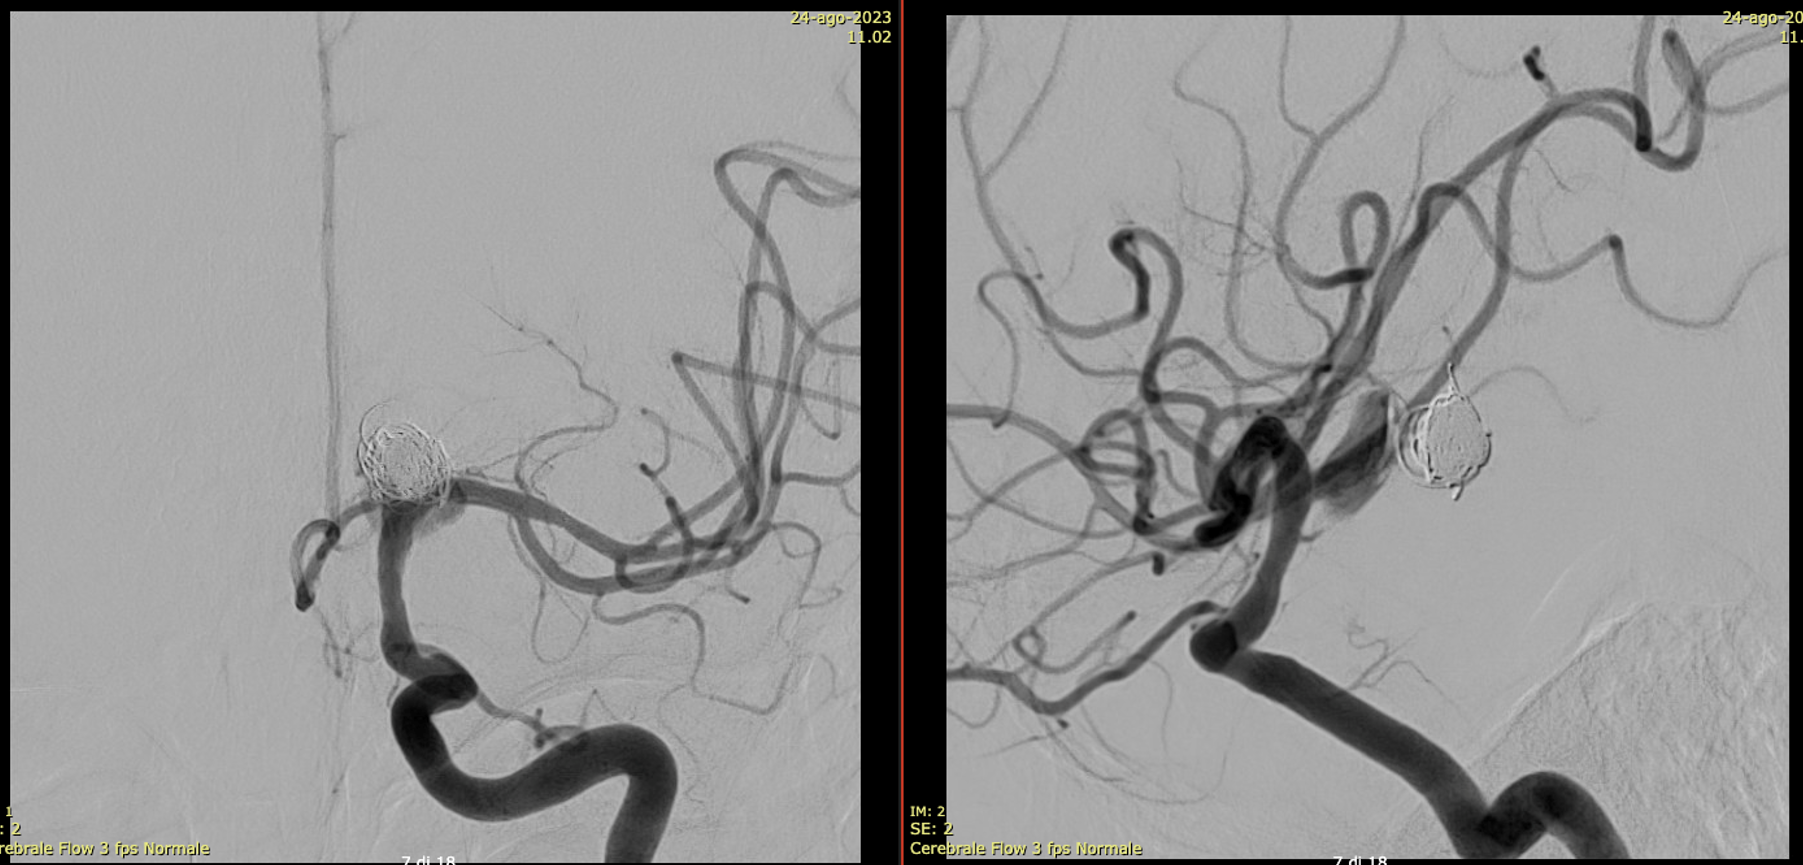

Very Important Case of Aggressive Basilar Bifurcation Aneurysm

Unruptured basilar tip aneurysm treated in 2010 with PED between right P1 and basilar.

Make sure you don’t judge — we know much more about how these behave now than in 2010 — and many people today still coil these with laser-cut stents and mess up options for the guaranteed recurrence

The aneurysm was kept open by the left (contralateral) PCom — again, we know this much better now than in 2010. And its very important.

13 year later. The aneurysm was mostly thrombosed and was growing, becoming symptomatic. The good old analog Philips workhorse is gone… Welcome to the digital world or Azurion

With manual compression of the left carotid — look how important manual compression or Balloon Test Occlusion can be

Left ICA — the preferential supply to bilateral SCAs is clearly seen

3D reconstructions of the left ICA (3D 5 seconds acquisition, 22 cm FOV, manual injection of pure contrast – 300 mg/ml – with a 20 ml syringe, no secondary reconstructions). Both the SCAs are injected by the PCom and the right SCA origin is shaped by the PED in right P1. Now in left P2 there is a fusiform dilatation, not present before